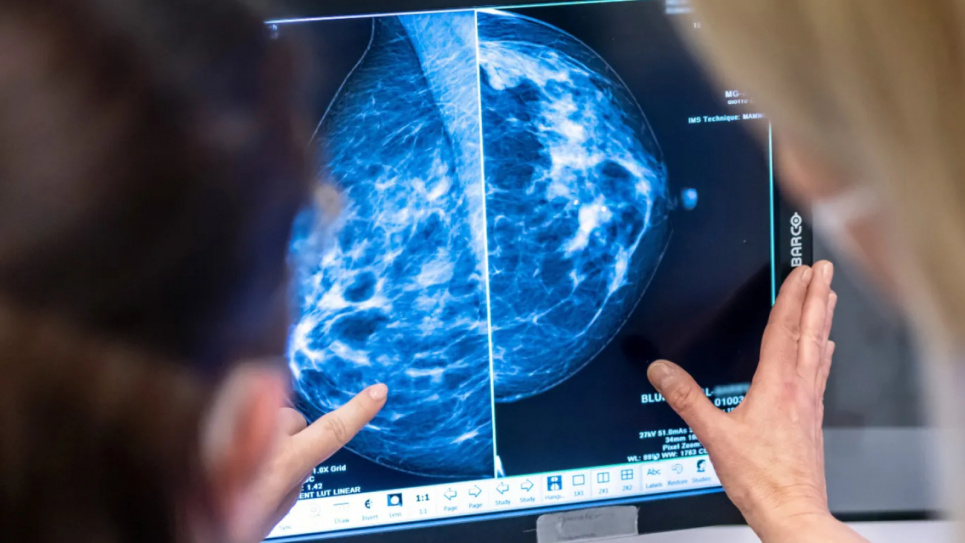

Фото: Swissinfo.chУчастие в программах раннего выявления рака молочной железы значительно снижает уровень смертности от этого заболевания. По данным экспертов, маммография помогает выявлять опухоли на очень ранней стадии, что существенно улучшает шансы на выздоровление. Об этом рассказывает Die Zeit.

В рамках программ раннего выявления женщины могут проходить рентген груди каждые два года. Такие методы визуализации способны выявить даже очень маленькие опухоли. Женщины, имеющие симптомы или подозрения на рак молочной железы, также проходят маммографию в рамках общего медицинского обслуживания.